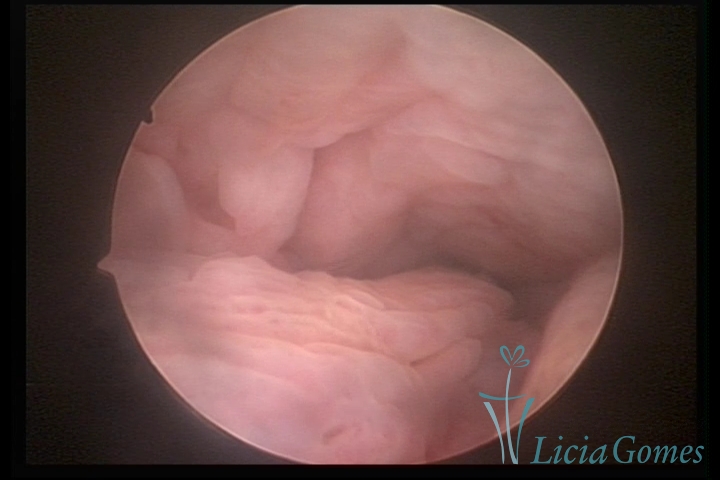

Third part or upper section

Presents the mucosa with a smooth, poorly vascularized surface, to the internal orifice